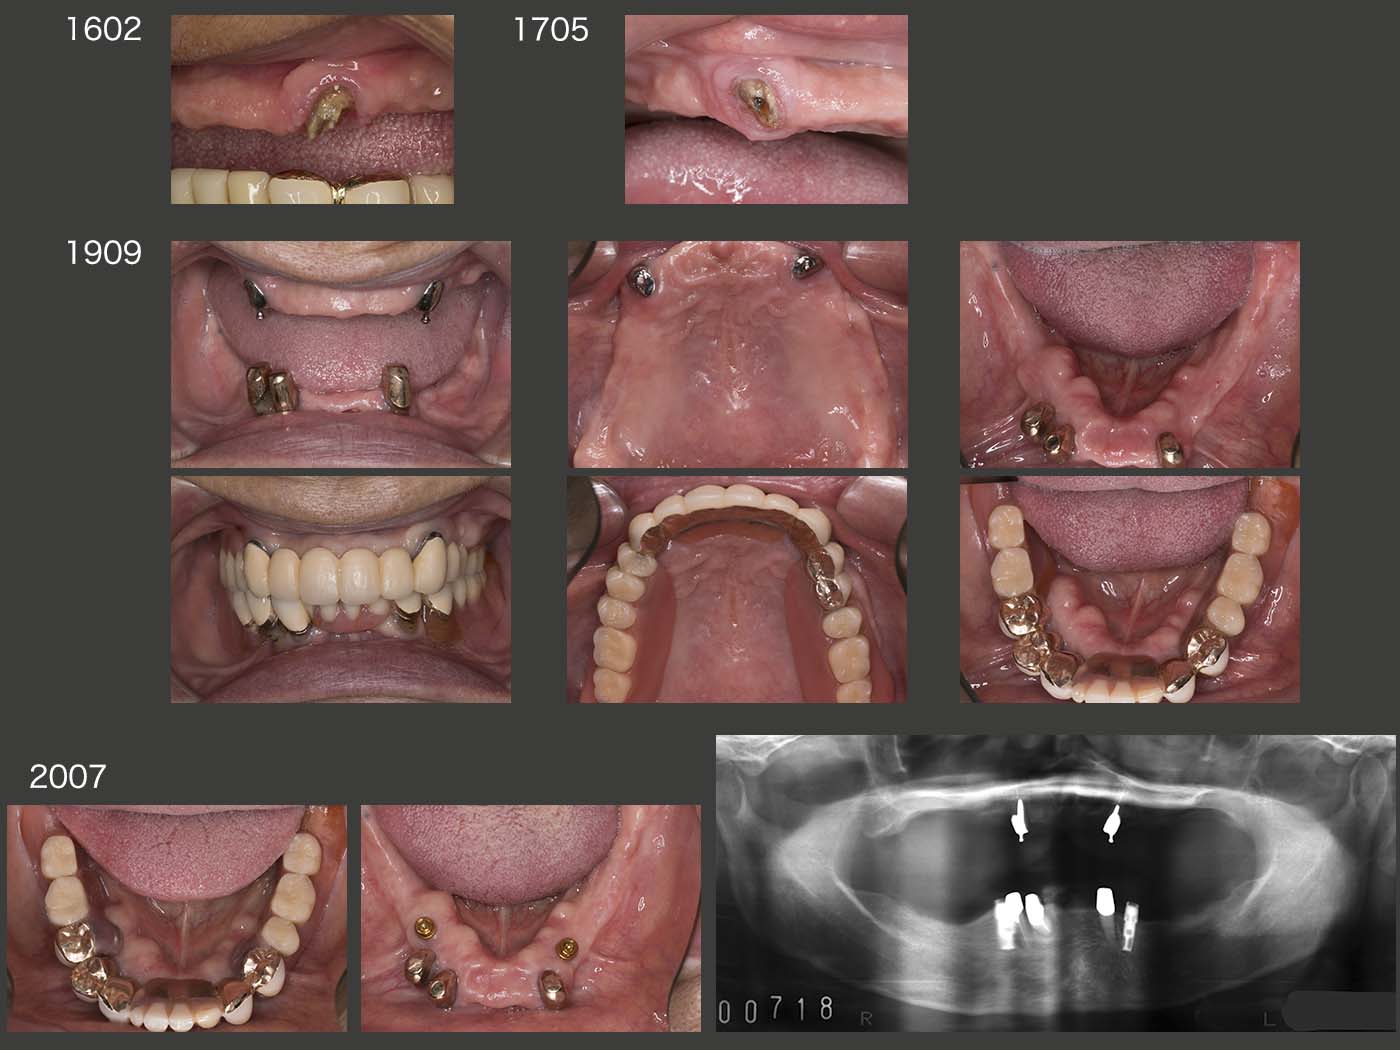

2018年12月までの5年4ヵ月間,特に問題なく経過した.しかし,19年7月,左上5の内冠が歯冠破折した.本来なら抜髄して,根管保持の補綴装置を製作するところであるが,今回は有髄のままOPAアタッチメントを装着した.(どこまで保てるか疑問ではあるが)なお,装着時に患者さんから左上3も外れていると言われたが,本当に左上3の内冠も歯冠破折していた.こちらはまだ歯肉縁上歯質が残っていたので,ピンを用いて内冠を再合着した.

2019年11月の状態.それにしても,有髄歯が2本続けて歯冠破折するとは想像していなかったとともに,有髄のままリカバリーできて本当に良かった.12年の時に心配した右上4は,両側性設計にすることで連結固定効果が強固になったことが幸いしたからか,その後小康を保っている.

上段のスライドは,コーヌス義歯装着後25年経過した2014年9月の状態.初診終了時上顎は6本,下顎は7本歯が残っていたが,14年には上顎は2本,下顎は3本と,この25年の間に合計8本の歯を失った.しかし,上下顎のコーヌス義歯は25年経過してもなお使用することができた.このように,将来に変化に対応できることがコーヌス義歯の利点の一つである.

しかし,15年9月,上顎左右犬歯のマージン部の2次カリエスが大きくなり,また内外冠の維持力の低下がみられたため,上顎義歯を再製作せざるを得なかった.下顎は,上顎の新義歯に合わせて人工歯を交換したりしているが,昔のままの義歯を使用し続けている.

2016年2月に左上3,17年5月に右上3それぞれの内冠が立て続きにコアごと脱離した.15年の内外冠再製作の際,前のままのコアを使用したが,う蝕がコアの内部にまで侵食していたのかもしれない.何度か内冠を再合着したが,19年9月,OPAアタッチメントに変更した.外冠がそのまま再利用でき,根面アタッチメントの周囲を開放できることから,コーヌス冠のリカバリーによく利用している.

また,19年9月の時点で,下顎の残存歯が風前の灯火の状態であった.下顎の総義歯の維持安定は相当難しいことから,いつ総義歯になっても構わないように,11月に2本のインプラントを埋入した.20年7月,まだ下顎残存歯は使用可能とのこと.インプラントの出番はまだない.